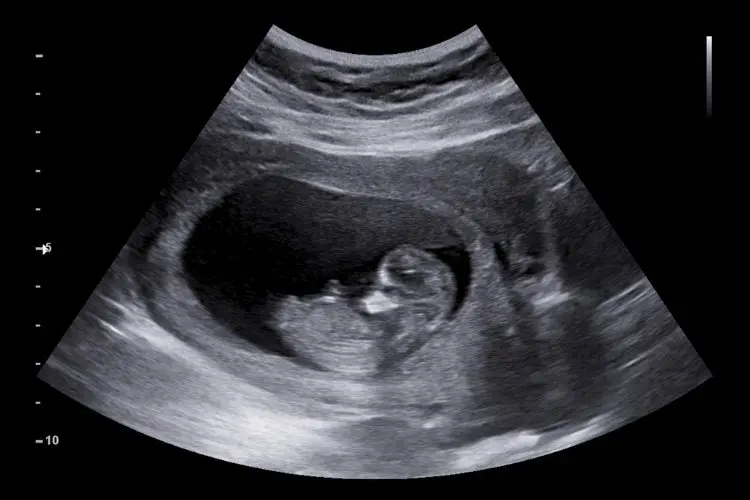

Der dritte Ultraschall in der Schwangerschaft, auch bekannt als Feindiagnostik oder Organultraschall, findet in der Regel zwischen der 20. und 2Schwangerschaftswoche statt. Dieser Ultraschall ist ein wichtiger Bestandteil der pränatalen Vorsorge, da er detaillierte Einblicke in die Entwicklung des ungeborenen Kindes ermöglicht und mögliche Auffälligkeiten frühzeitig erkennen kann.

Im Fokus dieses Ultraschalls stehen die Organe des Kindes, insbesondere das Herz, der Gehirn, die Lunge, die Magen-Darm-Trakt, die Nieren und die Blase. Zusätzlich werden die Plazenta und die Nabelschnur untersucht.

Der dritte Ultraschall ist eine wichtige Untersuchung in der Schwangerschaft, die detaillierte Einblicke in die Entwicklung des ungeborenen Kindes ermöglicht. Die Untersuchung findet in der Regel zwischen der 20. Und 2Schwangerschaftswoche statt und umfasst die Untersuchung aller Organe des Kindes.